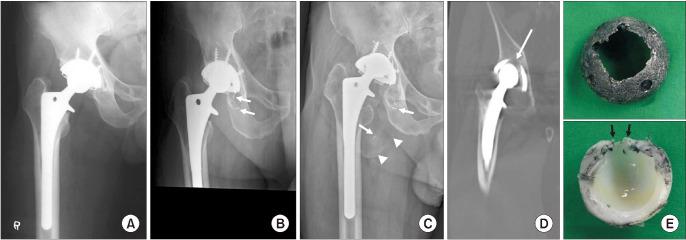

HHS 从术前的 46.5 分提高到术后的 81.8 分(<0.001)。平均线性磨损率为 0.36mm/年。共有 34 髋(56%)进行了翻修:10 髋(16.4%)进行了股骨假体翻修,9 髋(14.8%)进行了髋臼杯翻修,8 髋(13.1%)仅更换了关节面,7 髋(11.5%)进行了所有组件的翻修。术后 34 年,髋臼杯因无菌性松动而进行翻修的估计生存率为 90.9%,股骨假体因无菌性松动而进行翻修的估计生存率为 80.5%,任何原因进行翻修的估计生存率为 22.1%。

结论

HG 假体 THA 在术后 34 年时,髋臼和股骨假体的估计生存率较高,临床结果良好。与轴承相关的问题,如骨溶解和衬垫分离,占翻修手术的 56%,是 50 岁以下患者的关注点。